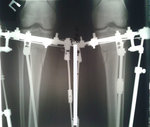

Дата операции 03.12.2015г.

Исходник - 51 год.

У пациентки начальная стадия артроза, остеопороз, протрузия диска L5- S1